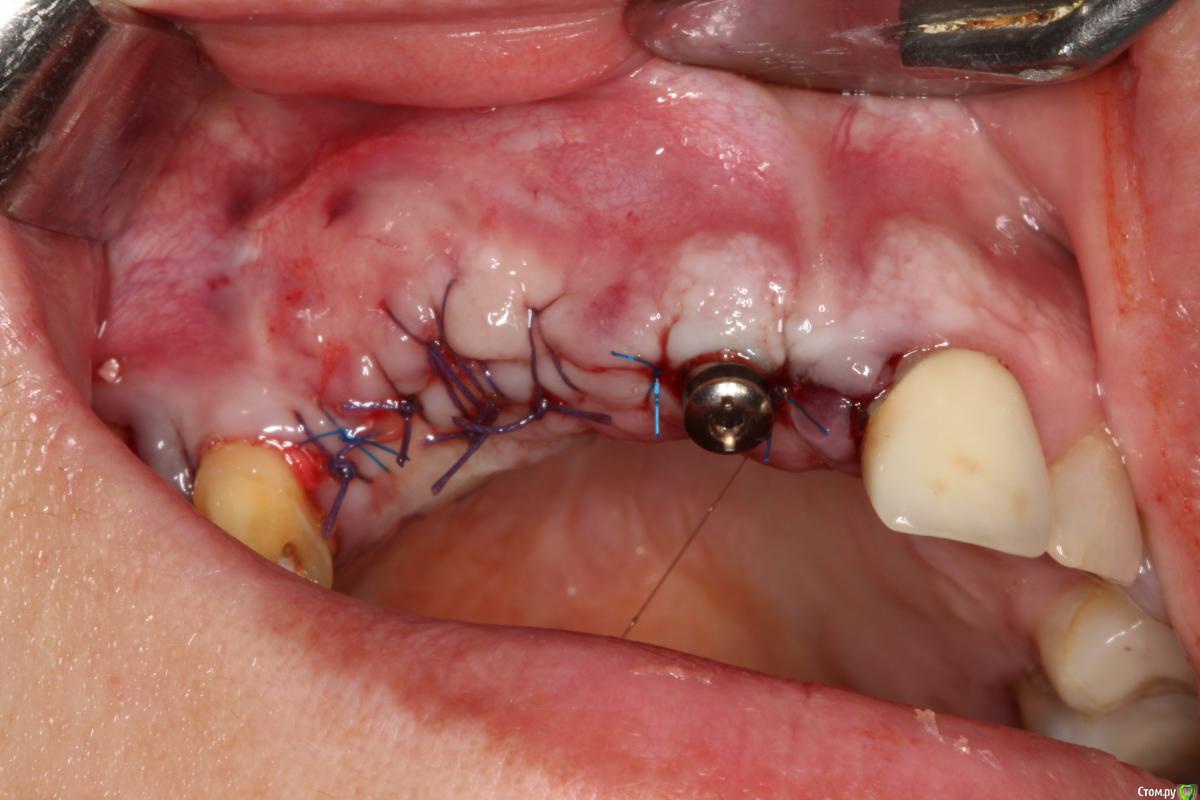

Robinbobin Опубликовано 9 сентября, 2015 Поделиться Опубликовано 9 сентября, 2015 Зуб 1.1 удалил,кюретаж и одномоментно установлен имплантат, заполнил MP3 и закрутил заглушкуУстановил имплантаты в области 1.3,1.4 подсыпал так же MP3 под мембрану и запинилЕсли покажите пальцем на ошибки буду благодарен))) 4 Ссылка на комментарий

колесников Опубликовано 9 сентября, 2015 Поделиться Опубликовано 9 сентября, 2015 Одномоментно желательно глубже ставить ,до 2мм по гребню уходит в последствии. У 12 обязательно сст . Впрочем можно было и в обл 13,14 им обойтись,но это дело вкуса. П-образный шов препочтителен,не будет расхождений и дополнительный объем на вершине получается. Ссылка на комментарий

Robinbobin Опубликовано 14 сентября, 2015 Автор Поделиться Опубликовано 14 сентября, 2015 ставить нужно учитывая шейку будущего зуба, а не глубже "потому что часть кости уйдет" Тут будет некрасивая ортопедия.СпасибоОртопедию обязательно выложу и покажу))) 1 Ссылка на комментарий